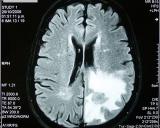

Недавнее исследование ученых Нагойского университета, Япония показало, что микроРНК в моче можно использовать как биомаркер для диагностики опухолей головного мозга. Свои результаты они представили в журнале...